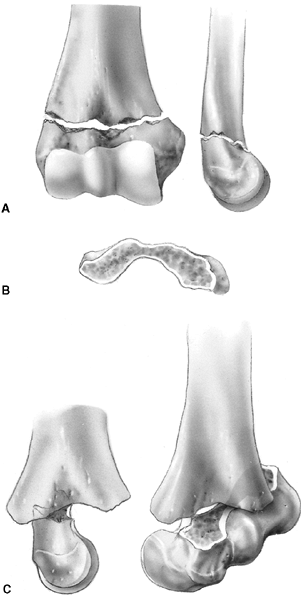

similar to adult acromioclavicular separation. A fall onto the point of

the shoulder drives the acromion and scapula distally. This results in

distal clavicular physeal separation. This is because the distal

epiphysis of the clavicle remains a cartilaginous cap until the age of

20 years or older (95), whereas the

acromioclavicular and coracoclavicular ligaments are firmly attached to

the thick periosteum of the clavicle. Typically, the lateral metaphysis

displaces through the injured dorsal periosteum, leaving the ligaments

intact and the epiphyseal end of the clavicle reduced in the

acromioclavicular joint (99) (Fig. 33.11).

Because these injuries represent physeal disruption with herniation of

bone from the periosteal tube, tremendous potential for healing and

remodeling exists.

![]() |

|

Figure 33.11

Lateral clavicle fracture-separation. The swelling and dorsal prominence of the clavicle may suggest an acromioclavicular separation. However, the distal epiphysis of the clavicle and acromioclavicular joint remain reduced. New bone forms from the periosteum, with subsequent remodeling of the prominence. (From Ogden J. Distal clavicular physeal injury. Clin Orthop 1984;188:68, with permission.) |